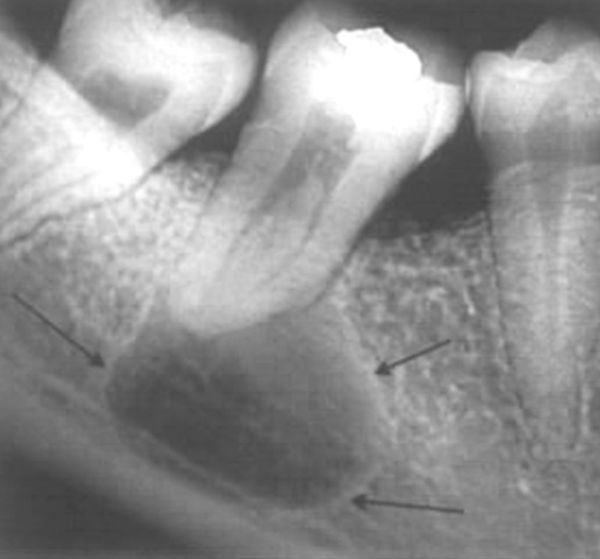

Прицельная рентгенограмма/радиовизиограмма. При наличии радикулярной кисты на рентгенограмме видно разрушение костной ткани округлой формы. Контуры разрушения чёткие и ровные, так как растущая киста постепенно оттесняет кость. Иногда киста распространяется на несколько зубов. Если киста большая, на снимке она может быть видна не полностью.

![Радикулярная киста на рентгенограмме [21] Радикулярная киста на рентгенограмме [21]](/media/bolezny/kista-zuba/radikulyarnaya-kista-na-rentgenogramme-21_s.jpeg)

Радикулярная киста на рентгенограмме [21]